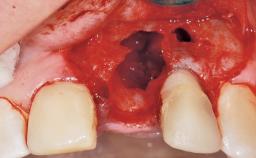

Immediate Placement of an Implant in a Maxillary Left Central Incisor Site

A 33-year-old female patient presented with an upper left central incisor that required extraction after a failed endodontic therapy. The tooth had been traumatized when the patient was a teenager and had undergone several endodontic treatments, including two apicectomy procedures. The patient was in good health and did not smoke. Clinical examination showed that the patient had a high lip line. In full smile, the gingival margins of the upper teeth were visible to the first molars. The gingival margins of central incisors 11 and 21 were only just showing. Examination of tooth 21 confirmed that the tooth was mobile and had hypererupted by 1 mm.

Socket Integrity Damage to one or more bone walls

Bone Volume Damage to one or more socket walls